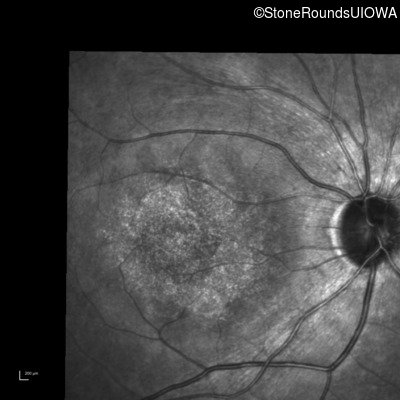

AR Stargardt Disease (IIA)

AR Stargardt Disease (IIA)

| Age at visit: 12 years |

| Age at visit: 13 years |

| Age at visit: 15 years |